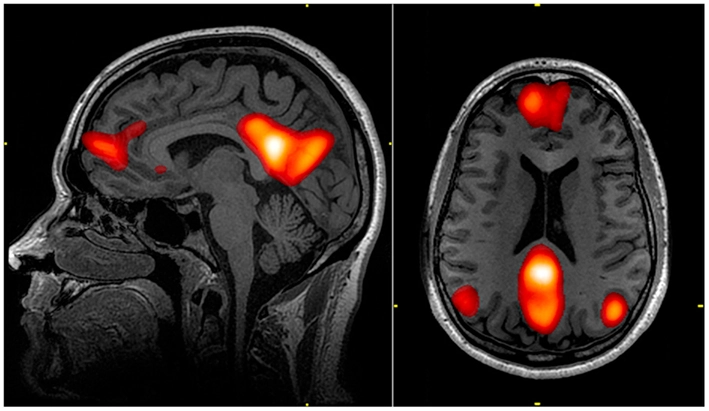

Our brain architecture is very revealing of our "thought process". What you see here is an fMRI image of the Default Mode Network. The red area in back is called the "posterior cingulate cortex".

How it works, is like this: all of our sense feed into the inferior temporal cortex, which recognizes, identifies, and names objects. Once an object has been identified, two additional calculations take place, "where" is it, and what "value" does it have. The value is context sensitive, the same object can have different values in different situations. Then these three elements get combined in the posterior cingulate cortex, where they get formatted into an "episodic memory".

The part that calculates value is the part in front in the image, it's the prefrontal cortex. "How" this information gets separated and then recombined is a fascinating story. Basically though, the value determining part of the circuitry runs the show. Humans use "strategies" for thought processes, and which strategy is in use is determined by what value it has. When a strategy being used has no further value, it's discarded in favor of another.

The map of strategies is a "graph neural network", if you've studied computer science you know a lot about graphs. There are algorithms for finding paths through graphs (basically like navigating a maze), algorithms for calculating the optimal path based on cost or expected reward or situational constraints, algorithms for partitioning graphs (like graph coloring problems and max-cut), and so on. A GNN can do all this and more, it becomes aware of the topology of graphs as it learns, so for instance if you have symmetries in your strategies the GNN will find them and make them available to you.